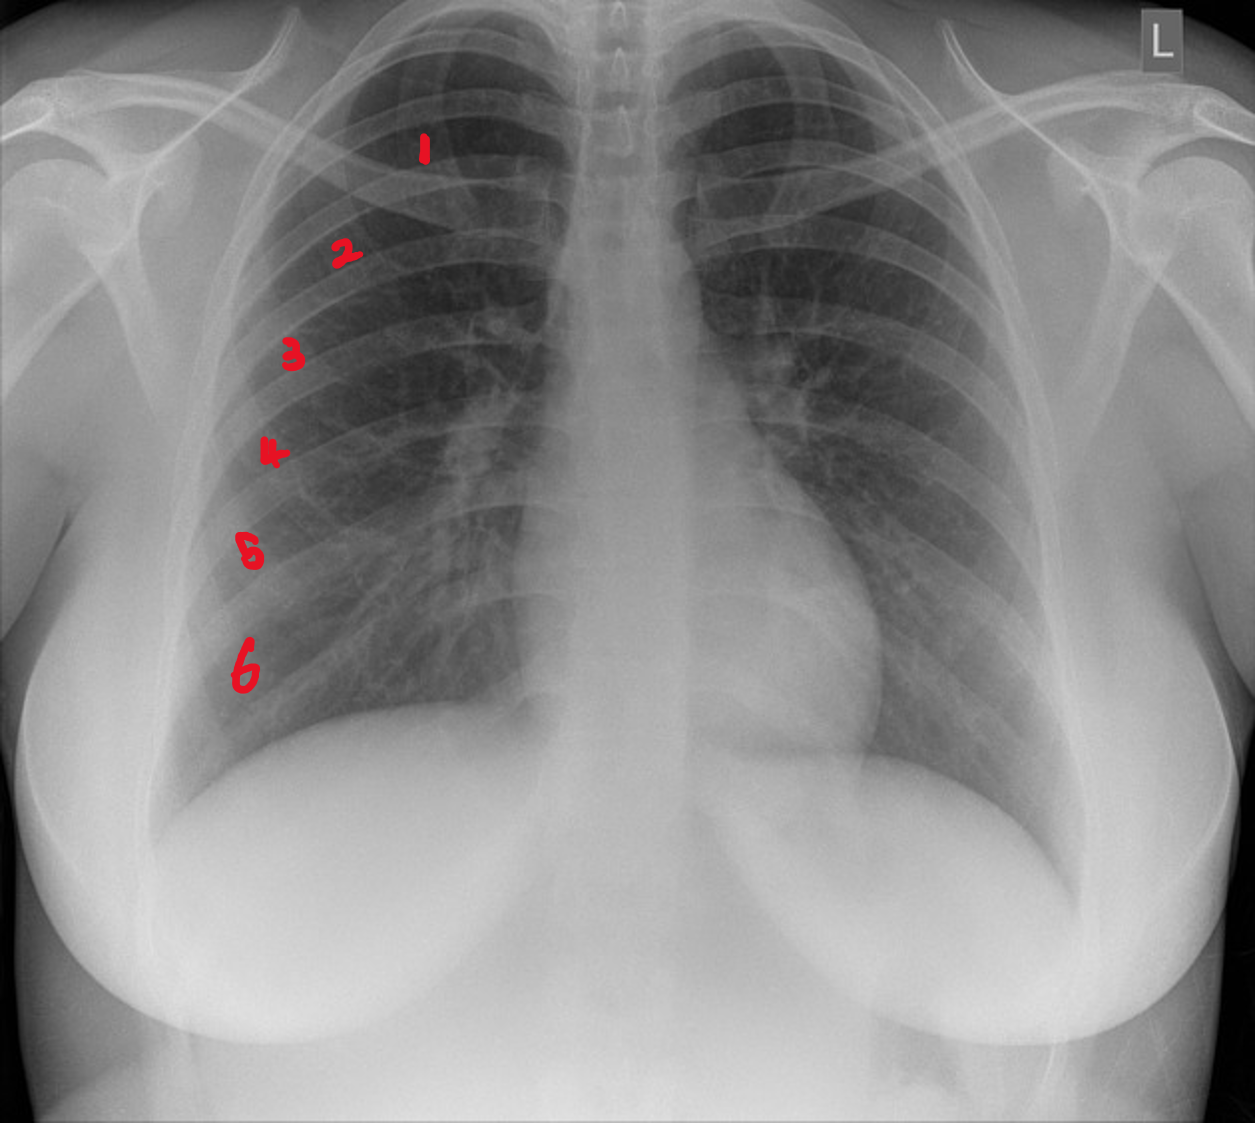

Inspiration

This is to check whether the patient took a deep breath during the X-ray.

On good inspiration, 5 - 6 anterior ribs should be visible.

If more ribs are visible, this could indicate hyperinflation for example in the case of COPD.

If the patient was not able to take a deep breath, then there will be fewer ribs visible.

CXR with anterior ribs marked.